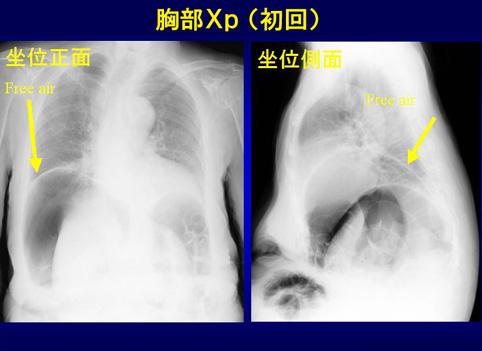

疾病(病理主体)的分类肿瘤样病变/肠管囊肿性气肿症

检查方法X线